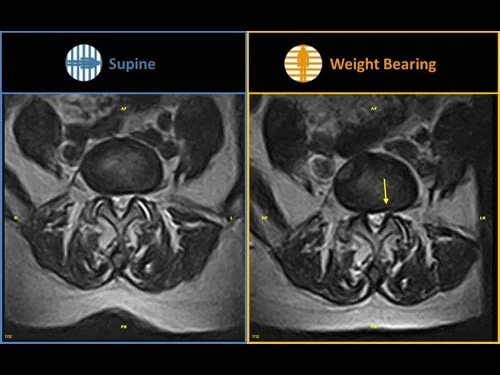

Конструкция аппарат позволяет переводить пациента из горизонтального в вертикальное положение. Это дает возможность проводить исследования позвоночника при естественной весовой нагрузке, что значительно повышает быстроту и точность диагностика, поскольку визуализируется фактическое состояние патологий.

Уникальная система поворота магнита, которая позволяет изменять положение пациента в диапазоне 90 градусов, и проводить диагностику в условиях естественной весовой нагрузки